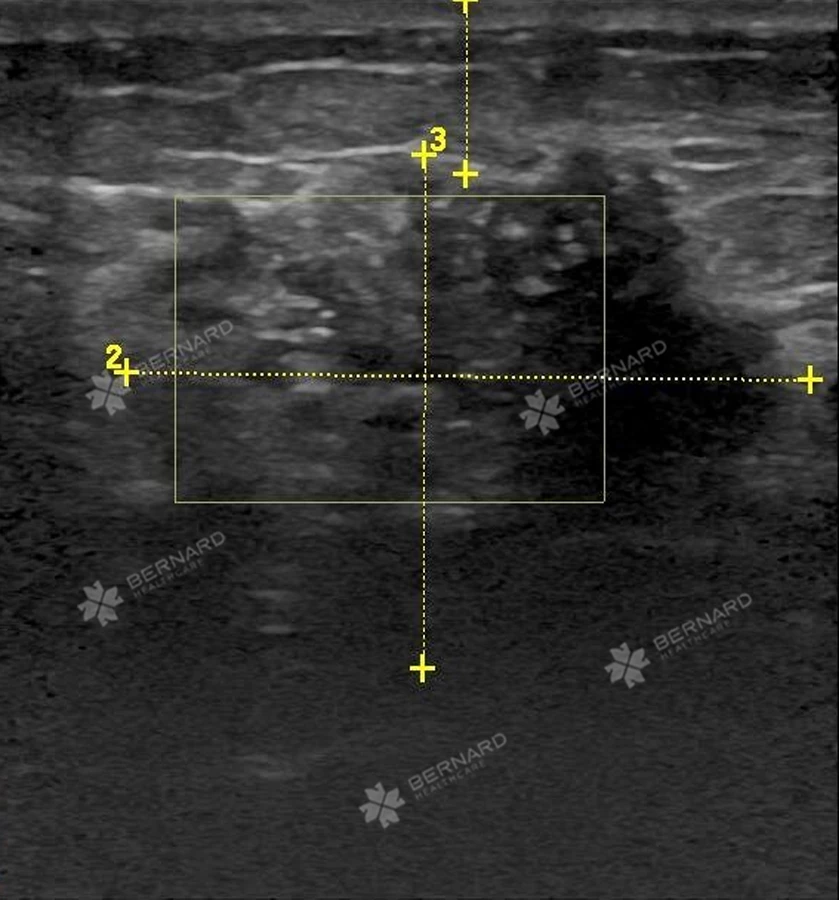

Trong đợt khám sức khỏe lần này, bệnh nhân được bác sĩ Bernard thuyết phục thực hiện các cận lâm sàng chuyên sâu để đánh giá lại tình trạng bệnh lý. Kết quả siêu âm vú cho thấy, tình trạng bệnh đã trầm trọng hơn năm trước:

Cụ thể tại vị trí 7h, cách núm vú trái 2cm, cách mặt da d# 8mm, có cấu trúc echo hỗn hợp dạng đặc, kích thước 33x27x32mm, vùng đáy có thoái hóa nang kích thước, 22x12mm, trục ngang, bờ tua gai có vôi hóa đa hình, tăng sinh mạch máu bên trong, phân loại BIRADS 5.

Bác sĩ Bernard đã thực hiện sinh thiết lõi kim (core-biopsy) cho sang thương BIRADS 5 tại tuyến vú trái. Kết quả giải phẫu mô bệnh học cho thấy: Sự tăng sản tế bào tuyến nhân dị dạng ái kiềm, tỉ lệ N/C > 1, gián phân bào không điển hình, tế bào xếp thành đám ổ.